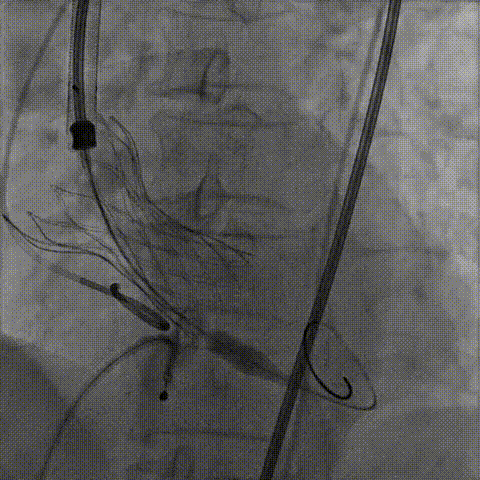

手术影像:

左侧作为主入路置入大鞘

主动脉根部造影

输送器柔顺过弓、跨瓣

瓣膜开始定位

瓣膜逐步释放到工作位

瓣膜工作位造影,位置良好

瓣膜完全释放

瓣膜膨胀不良

瓣膜膨胀不良进行球囊后扩

球囊后扩后造影无漏